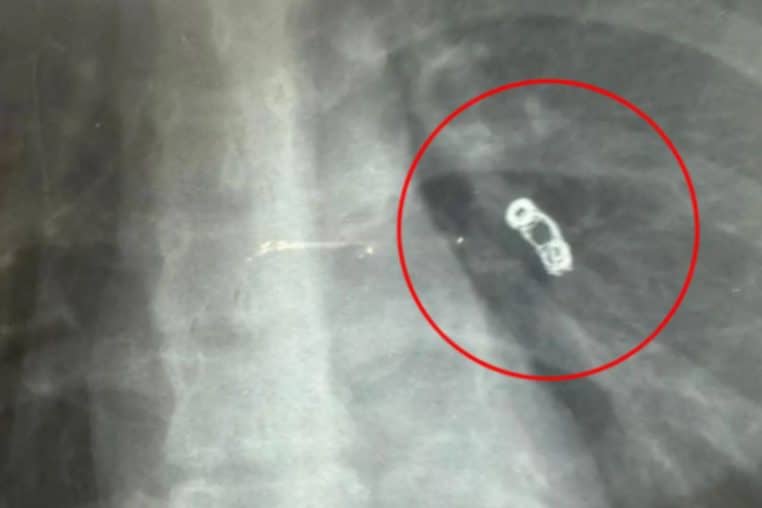

En réalité, d’après Jam Press, Ekaterina Badulina avait un corps étranger dans les poumons. C’est lors d’une radio que les médecins ont découvert un objet métallique dans son corps.

« Les médecins ont vu une sorte de ressort métallique »

« Il s’avère que sur la photo, les médecins ont vu une sorte de ressort métallique mesurant 5 sur 16 millimètres, qui se trouvait dans le poumon », a-t-elle déclaré.